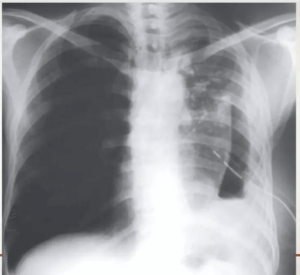

• ⁠ ⁠Xray showing cavitatory consolidation in right upper lung zone and multiple ill-defined nodules in both lungs

CAVITATION AND TREE IN BUD SIGN IS INDICATIVE OF AN ACTIVE DISEASE PROCESS AND USUALLY HEALS S A LINEAR OR FIBROTIC LESION.